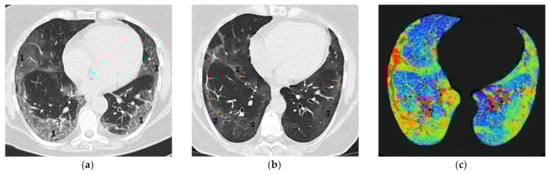

- Anghel, A.-M.; Niculae, C.-M.; Manea, E.-D.; Lazar, M.; Popescu, M.; Damalan, A.-C.; Bel, A.-A.; Nedelcu, I.-M.; Patrascu, R.-E.; Hristea, A. The Impact of Tocilizumab on Radiological Changes Assessed by Quantitative Chest CT in Severe COVID-19 Patients. J. Clin. Med. 2022, 11, 1247. [Google Scholar] [CrossRef]